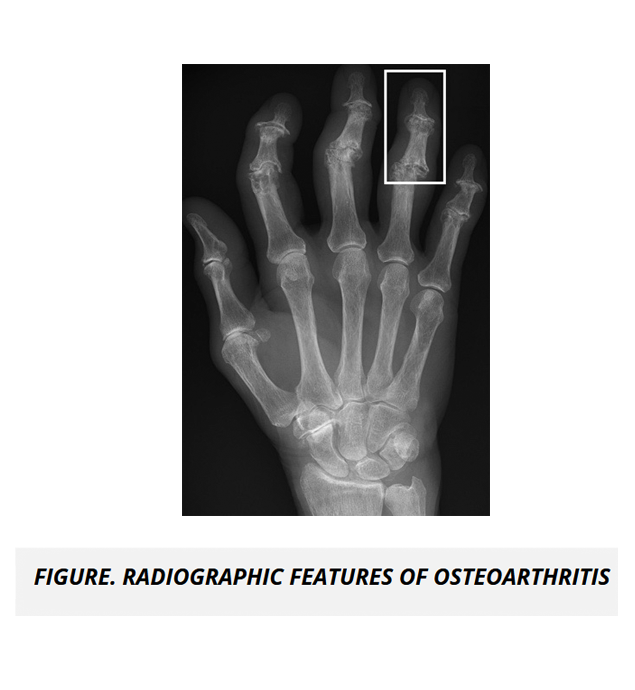

Rheumatology and Musculoskeletal Content Review 6% - 10%

The course features detailed tables and high quality radiologic and gross images to help you conceptualize the application of medicine for normal and abnormal body system processes and pathologies in rheumatology and the musculoskeletal system.

• Diseases of Joints